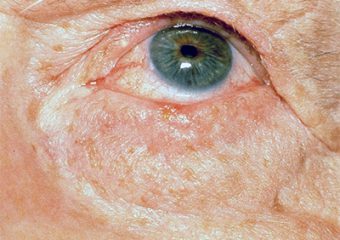

Melanoma Photos

Amelanotic melanomas may be pinkish-looking, reddish, purple, normal skin color or essentially clear and colorless.